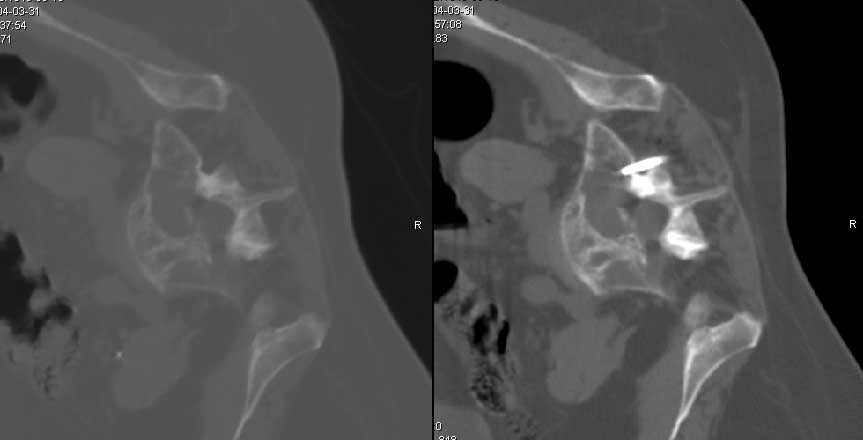

CT - důležité při postižení axiálního (osového) skeletu, stanovení stability, porušení kontinuity zadních elementů páteře

Cementoplastika - do osteolytické léze je perkutánní technikou aplikován kostní cement. Kontraindikací je vyplnění léze, která zasahuje do kloubu nebo intervertebrálního disku.

Cementoplastika může výhodně navazovat na předcházející RFA - provedení stabilizace osteolytické léze.

Vertebroplastika - podstatou metody je vyplnění obratlového těla (infiltrace) speciálním kostním cementem.

Kyphoplastika - metoda je obdobná jako vertebroplastika, ale před aplikací kostního cementu je pomocí speciálního nástroje vytvořená kavita (dutinka) v obratlovém těle nebo v osteolytickém ložisku. Tím může dojít k reparaci výšky obratlového těla. Při zavedení do osteolytické léze tato provedená komprese vytvoří tlakový uzávěr odvodných žil. Druhou výhodou je, že aplikovaný kostní cement není tekutý, má konzistenci "žvýkací gumy", a proto jen minimálně může dojít k úniku kostního cementu mimo oblast zájmu.